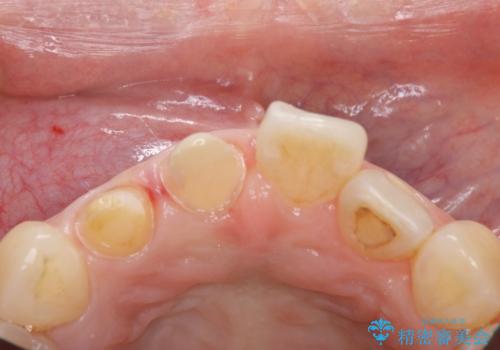

- 昔治療したプラスチックの材料が目立つから、セラミックで被せたいということを主訴で来院された患者様です。

虫歯治療をし、仮歯を制作し、オールセラミック(スタンダード)にて治療させていただきました。